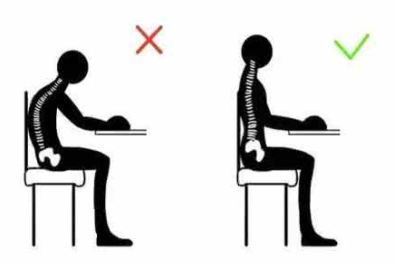

關(guān)于腰椎間盤突出  腰椎間盤突出癥是纖維環(huán)破裂后髓核突出壓迫神經(jīng)根造成以腰腿痛為主要表現(xiàn)的疾病。腰椎間盤退行性改變或外傷所致纖維環(huán)破裂,髓核從破裂處脫出,壓迫腰椎神經(jīng),從而出現(xiàn)腰腿放射性疼痛。  病因: 一、退行性變: 目前認(rèn)為,其基本病因是腰椎間盤的退行性變。退行性變是一切生物生、長、衰、亡的客觀規(guī)律,由于腰椎所承擔(dān)的特殊的生理功能,腰椎間盤的退行性變比 其他組織器官要早,而且進(jìn)展相對要快。這個過程是一個長期,復(fù)雜的過程。所謂腰椎間盤退行性改變:即由于椎間盤受體重的壓迫,加上腰部又經(jīng)常進(jìn)行彎曲、后伸等活動,易造成椎間盤的擠壓和磨損,尤其是下腰部的椎間盤,從而產(chǎn)生退行性改變。腰椎間盤退行性改變是本病發(fā)生的基礎(chǔ)。 二、其他因素: 1、外力作用:在日常生活和工作中,部分人往往存在長期腰部用力不當(dāng)、過度用力姿勢或體位的不正確等情況。例如長期從事彎腰工作的煤礦工人和建筑工人需經(jīng)常彎腰提舉重物。這些長期反復(fù)的外力造成的損傷日積月累地作用于椎間盤,加重了退變的程度。 2、椎間盤自身解剖因素的弱點: (1) 椎間盤在成人之后逐漸缺乏血液循環(huán),修復(fù)能力也較差,特別是在退變產(chǎn)生后,修復(fù)能力更加微弱。 (2) 椎間盤后外側(cè)的纖維環(huán)較為薄弱,而后縱韌帶在腰5、骶1平面時寬度顯著減少,對纖維環(huán)的加強(qiáng)作用明顯減弱。 (3) 腰骶段先天異常:腰骶段畸形可使發(fā)病率增高,這些異常造成椎間隙寬度不等,并常造成關(guān)節(jié)突出,關(guān)節(jié)受到更多的旋轉(zhuǎn)勞損,使纖維環(huán)受到的壓力不一,加速退變。 3、種族、遺傳因素:有色人種發(fā)病率較低,例如印第安人和非洲黑人等發(fā)病率較其他民族明顯要低。  2 病理 腰椎間盤突出癥的病理變化過程大致可分為三個階段: 1、突出前期:髓核因退變和損傷可變成碎塊狀物,或呈瘢痕樣結(jié)締組織,變性的纖維環(huán)可因反復(fù)損傷而變薄變軟或產(chǎn)生裂隙。此期病人可有腰部不適或疼痛,但無放射性下肢痛。也有的人原無病變,可因一次大的暴力引起髓核突出。 2、突出期:外傷或正常的活動使椎間盤壓力增加時,髓核從纖維環(huán)薄弱處或破裂處突出。突出物刺激或壓迫神經(jīng)根即發(fā)生放射性下肢痛,或壓迫馬尾神經(jīng)發(fā)生大小便功能障礙。在老 年患者,可因椎間盤退變,整個纖維環(huán)變得軟弱松弛,椎間盤可呈彌漫性向周圍膨出。 3、突出晚期:腰椎間盤突出后,病程較長者,椎間盤本身和其他鄰近結(jié)構(gòu)均可發(fā)生各種繼發(fā)性病理改變。 3 誘發(fā)因素 腰椎間盤突出癥的基本因素是椎間盤退變,但某些誘發(fā)因素可致使椎間隙壓力增高,引起髓核突出。此種誘發(fā)因素常與以下因素有關(guān): 1. 年齡因素:腰椎間盤突出癥的好發(fā)年齡在30-50歲,平均手術(shù)年齡在40歲,因此退變可能是其重要因素。 2. 身高與性別:有人認(rèn)為身材過高也會易發(fā)腰突癥,而男性發(fā)病率是女性的5倍。 3. 增加腹壓:臨床上有約1/3的病人在發(fā)病前有明確的增加腹壓的因素,如劇烈的咳嗽、噴嚏、屏氣、用力排便等。使腹壓增高,破壞了椎節(jié)與椎管之間的平衡狀態(tài)。 4. 不良體位:人在完成各種工作時,需要不斷更換各種體位以緩解腰部壓力,如長期處于某一體位不變,即可導(dǎo)致局部的累積性損傷。特別是長期處于不良姿勢更容易誘發(fā)本病。 5. 職業(yè)因素:重體力勞動者發(fā)病率最高,白領(lǐng)勞動者最低。汽車駕駛員由于長期處于顛簸和振動狀態(tài),椎間盤承受的壓力大且反復(fù)變化,也易誘發(fā)椎間盤突出。 6. 受寒受濕:寒冷或潮濕可引起小血管收縮、肌肉痙攣,使椎間盤的壓力增加,可能造成退變的椎間盤破裂。     癥狀: 腰椎間盤突出癥患者最多見的癥狀為疼痛,可表現(xiàn)為腰背痛、坐骨神經(jīng)痛,典型的坐骨神經(jīng)痛表現(xiàn)為由臀部、大腿后側(cè)、小腿外側(cè)至跟部或足背的放射痛。據(jù)臨床統(tǒng)計,約95%的腰突癥患者有不同程度的腰痛,80%的患者有下肢痛。特別是腰痛,不僅是腰椎間盤突出最常見的癥狀,也是最早出現(xiàn)的癥狀之一。    檢查: 1、X線:腰椎間盤所包括的髓核、纖維環(huán)和軟骨板密度均較低,在X線下并不顯影,因此臨床上腰突癥患者的腰椎X線平片可僅有一些非特異性的變化,甚至無異常變化。因此單純腰椎平片并不能作為有無腰椎間盤突出癥的直接依據(jù),但X線能發(fā)現(xiàn)腰椎的退行性改變和結(jié)構(gòu)異常,對提示椎間盤的退變有重要意義,并且能排除其他的一些腰椎疾患,如腰椎結(jié)核、腫瘤和腰椎滑脫等。典型的腰椎間盤突出癥患者通過病史、體征和X線平片即能作出初步的診斷。 2、CT檢查:腰椎的CT可以清楚地顯示椎間盤突出的部位、大小、形態(tài)和神經(jīng)根、硬脊膜受壓的情況,同時還可顯示黃韌帶肥厚、小關(guān)節(jié)增生、椎管和側(cè)隱窩狹窄等情況。對腰椎間盤突出癥診斷的準(zhǔn)確率達(dá)到80%-92%。 3、核磁共振(MRI):核磁共振沒有輻射,可以多方位成像(橫斷面、冠狀面、矢狀面和斜面),對解剖細(xì)節(jié)顯示較好,對組織結(jié)構(gòu)的細(xì)微病理變化更敏感(如骨髓的浸潤),可以排除神經(jīng)和脊柱腫瘤等。對于一些落到椎管的髓核組織也不會遺漏。 4、脊髓造影:脊髓造影利用椎管內(nèi)蛛網(wǎng)膜下腔的空隙,注入造影劑后在X線下攝片,顯示椎管內(nèi)部結(jié)構(gòu)。目前常用水溶性造影劑,能較清晰地顯示硬膜腔、馬尾神經(jīng)和神經(jīng)根鞘,對腰椎間盤突出癥的診斷可達(dá)90%左右,主要X線表現(xiàn)為硬膜囊壓迫征象和神經(jīng)根鞘壓迫征象。但由于CT和MRI在臨床的廣泛應(yīng)用,無創(chuàng)傷且診斷率更高,脊髓造影在臨床上的應(yīng)用已經(jīng)大大減少,而且由于它副作用較大,甚至可能造成截癱等嚴(yán)重情況,目前主張慎重選用。 5、肌電圖:肌電圖是對周圍神經(jīng)與肌肉的電生理檢查方法,可用于觀察并記錄肌肉在靜止、主動收縮和支配其的周圍神經(jīng)受刺激時的電活動,同時也可用來測量周圍神經(jīng)的傳導(dǎo)速度。在腰椎間盤突出癥上,肌電圖主要通過檢查雙下肢肌肉的興奮性來反映相應(yīng)神經(jīng)根的狀態(tài),并根據(jù)異常電活動的分布范圍來判斷椎間盤突出和神經(jīng)根受壓的節(jié)段。在脊神經(jīng)根和馬尾神經(jīng)受壓的病人,肌電圖陽性率可達(dá)80%-90%,但與CT和MRI相比并不是首選的檢查手段,可用于輔助診斷和判斷神經(jīng)根的受壓情況,同時也可以用來作為判斷治療后神經(jīng)根恢復(fù)情況的指標(biāo)之一。    預(yù)防: 腰椎間盤突出癥是在退行性變基礎(chǔ)上積累傷所致,積累傷又會加重椎間盤的退變,因此預(yù)防的重點在于減少積累傷。 日常注意事項: 1.平時要有良好的坐姿,睡眠時的床不宜太軟。 2.長期伏案工作者需要注意桌、椅高度,定期改變姿勢。 3.職業(yè)工作中需要常彎腰動作者,應(yīng)定時伸腰、挺胸活動,并使用寬的腰帶。 4.應(yīng)加強(qiáng)腰背肌訓(xùn)練,增加脊柱的內(nèi)在穩(wěn)定性,長期使用腰圍者,尤其需要注意腰背肌鍛煉,以防止失用性肌肉萎縮帶來不良后果。 5.如需彎腰取物,最好采用屈髖、屈膝下蹲方式,減少對腰椎間盤后方的壓力。    治療: (一)中醫(yī)外敷療法: 腰椎間盤突出可以外貼 腰突正骨膏,其有效成分可透入皮膚產(chǎn)生活血,止痛,化淤,通經(jīng)走絡(luò),開竅透骨,祛風(fēng)散寒等效果,并通過藥物的歸經(jīng)作用而調(diào)理機(jī)體陰陽平衡,滲透于表皮,刺激神經(jīng)末梢,促進(jìn)局部血液微循環(huán),扶正固本、改善體質(zhì),從根本上、全方位針對腰椎疾病病機(jī)特點而發(fā)揮療效,改善病變周圍組織營養(yǎng),起到修復(fù)骨病組織的作用,最終達(dá)到治療目的。 (二)自我治療: 1.腹肌鍛煉: 也就是仰臥起坐。每次做十個,每天三次。(可根據(jù)患者的體質(zhì)來定,不可逞強(qiáng))。 2.交叉扭腰: 兩腳分開與肩寬,腳尖向內(nèi)兩臂伸直,一手在體側(cè),一 手舉過頭頂。如果右手在上,先向左側(cè)后方擺。左側(cè)相反。于此同時腰部也隨之扭動,左右各100次。 3.抱膝觸胸: 處于仰臥位,雙膝屈曲,手抱住膝部,使盡量靠近胸部,然后放下,一上一下為一個動作,可持續(xù)30個。 4.腰背肌鍛煉: 處于平臥,雙膝彎曲放在床上,然后用力將臀部抬起,離開床面10厘米。這時您會感覺到腰背部在用力,堅持5秒鐘,反復(fù)10下。  (三)非手術(shù)治療: 非手術(shù)療法是治療腰椎間盤突出癥的基本療法,約80%以上的患者經(jīng)保守治療均可得到緩解和痊愈。其主要療法有: 1.日常家庭治療:早期腰椎間盤突出癥,癥狀輕微,不需要做特殊的治療。第一,注意臥床休息,避免腰椎受外力壓迫,第二,應(yīng)用其他方法積極鍛煉腰部肌肉力量。 2.牽引治療; 3.推拿按摩治療; 4.物理治療; 5.消炎鎮(zhèn)痛藥物; 6.減輕神經(jīng)根水腫藥物。 (四)推拿治療: 1.解除腰臀部肌肉痙攣 2.拉寬椎間隙,降低盤間壓力 3.增加椎間盤外壓力 4.調(diào)整后關(guān)節(jié),松解粘連 5.促使受損傷的神經(jīng)根恢復(fù)功能 (五)微創(chuàng)治療: 微創(chuàng)治療方法的目的是消除腰椎間盤突出的髓核以解除對神經(jīng)的壓迫。微創(chuàng)治療技術(shù)采用可視設(shè)備,創(chuàng)口不足一厘米有些甚至不足一毫米。消融或摘除髓核,從根本上解除致病因素,因而能夠取得很好的效果。 (六)手術(shù)治療: 腰椎間盤突出癥的手術(shù)原則是嚴(yán)格無菌操作,盡量保留不必去除的骨結(jié)構(gòu)和軟組織結(jié)構(gòu),以最小的創(chuàng)傷達(dá)到足夠的顯露,仔細(xì)徹底地去除病變組織,達(dá)到治療目的。   綠柏相關(guān)產(chǎn)品:  懸吊訓(xùn)練療法是康復(fù)醫(yī)學(xué)中以持久改善肌肉骨骼疾病為目的的,應(yīng)用主動治療和訓(xùn)練的一個總的概念整合,是一種運(yùn)動感覺的綜合訓(xùn)練系統(tǒng),包括診斷與治療兩大系統(tǒng)。 產(chǎn)品特點: 1.電腦軟件管理系統(tǒng),涵蓋患者信息管理、評估、訓(xùn)練、量表、報告、視頻教學(xué)六大模塊,輕松實現(xiàn)評估與訓(xùn)練一體化管理; 2.多點多軸設(shè)計,滿足不同治療方案設(shè)計; 3.懸吊工作站及各個懸吊點,均能實現(xiàn)任意位置移動,一鍵解鎖,省時省力; 4.實時力反饋,精準(zhǔn)量化弱鏈測試及懸吊治療全過程,給治療師及患者最直觀的效果呈現(xiàn); 5.智能神經(jīng)肌肉促通裝置,可根據(jù)評估結(jié)果設(shè)置治療模式、頻率、時間等相關(guān)參數(shù),讓懸吊康復(fù)更加高效有針對性; 6.外觀高端大氣,結(jié)構(gòu)穩(wěn)固,給患者安全保障,增加治療信心。  |